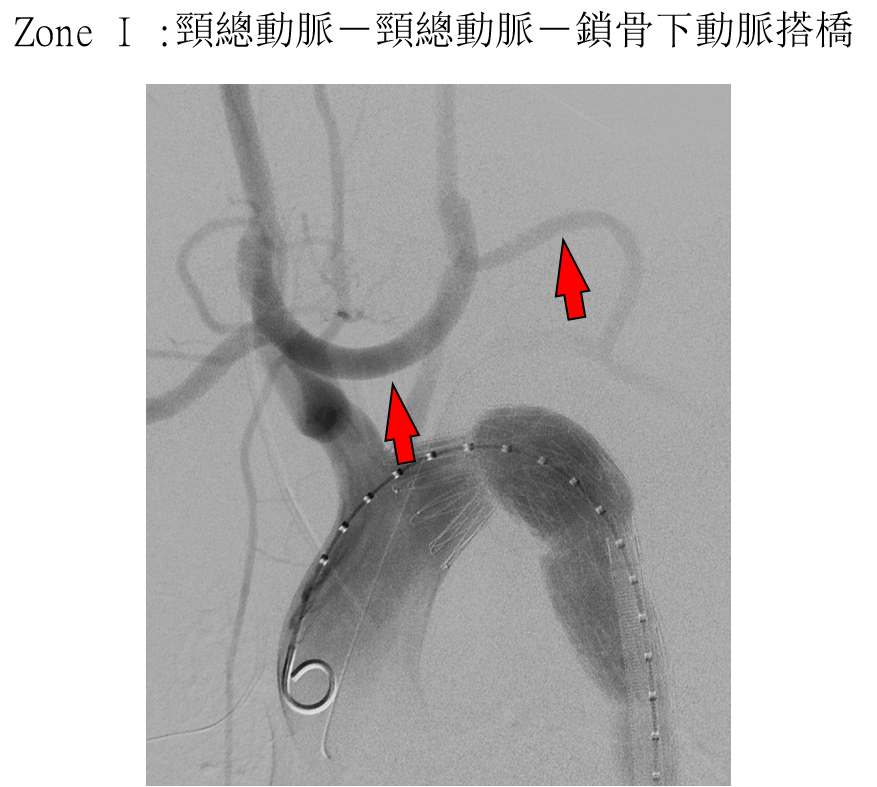

挑战Zone 0/1:突破解剖学禁区

更令人振奋的是,该器械已成功将适应症扩展至更近端的Zone 0(无名动脉)和Zone 1(左颈总动脉)。虽然这部分解剖结构更复杂,技术成功率(Technical Success)约为88.2%,但其早期结果依然令人鼓舞:

分支通畅率: 98.6%截瘫发生率: 0%

卒中风险: 约7.8%(主要与弓部操作扰动斑块有关)

图:ZONE 0/1 实验数据